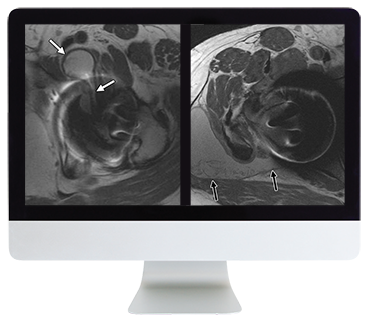

$ 399.00Original price was: $ 399.00.$ 79.00Current price is: $ 79.00.ARRS Controversies In Hip And Pelvis Imaging 2016 ARRS Controversies In Hip And Pelvis Imaging 2016 (CME VIDEOS) This Online Course provides established principles and new concepts regarding pathology of the hip and pelvis, with an emphasis on MRI. Lectures cover a number of clinically important topics, including pitfalls and […]